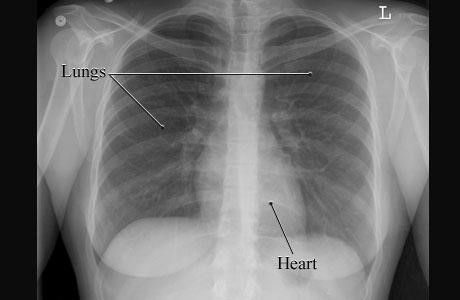

¿Es segura la radiación médica de diagnóstico?

Chest X ray - St Vincent's Lung HealthSeguridad y Radiación La radiación de fondo existe naturalmente en todas partes del medio ambiente. Estos niveles de radiación de fondo son claramente seguros. Si no lo fueran, la vida en la Tierra no prosperaría. Sin embargo, sabemos que la radiación tiene el potencial de causar cáncer.

El potencial de cáncer inducido por la radiación depende de la cantidad de exposición a la radiación y la acumulación de la exposición durante un tiempo prolongado. Los niveles de exposición más bajos (radiación de fondo, exámenes de medicina nuclear, tomografías computarizadas (TC) o radiografías de diagnóstico) conllevan riesgos bajos.

Después de 100 años de investigación, ha sido imposible probar que las radiografías de diagnóstico de dosis baja única causen cáncer. Es importante usar exámenes de diagnóstico solo cuando sea necesario. Un examen necesario es seguro.